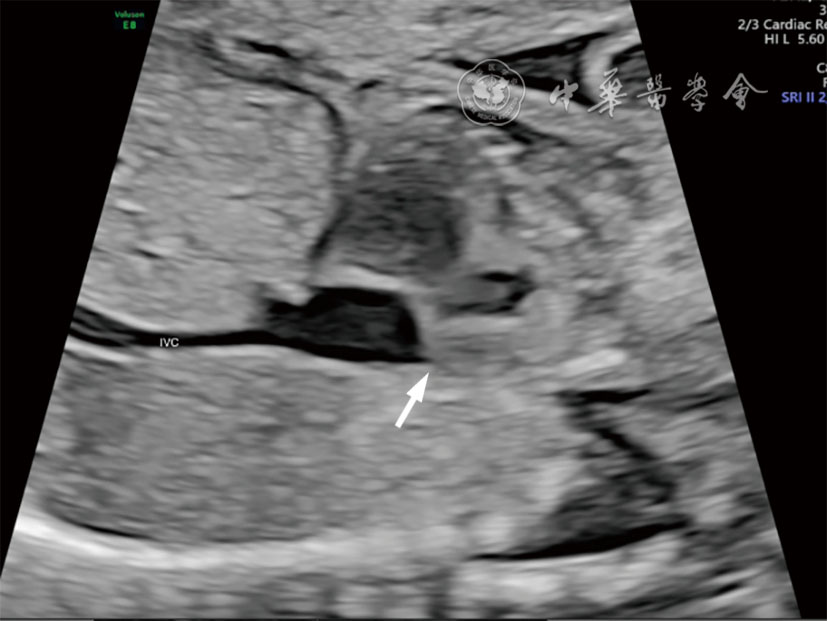

图3 二维超声图像示上下腔静脉矢状切面未探及上腔静脉纵切面 注:IVC为下腔静脉;箭头所示为上腔静脉未显示